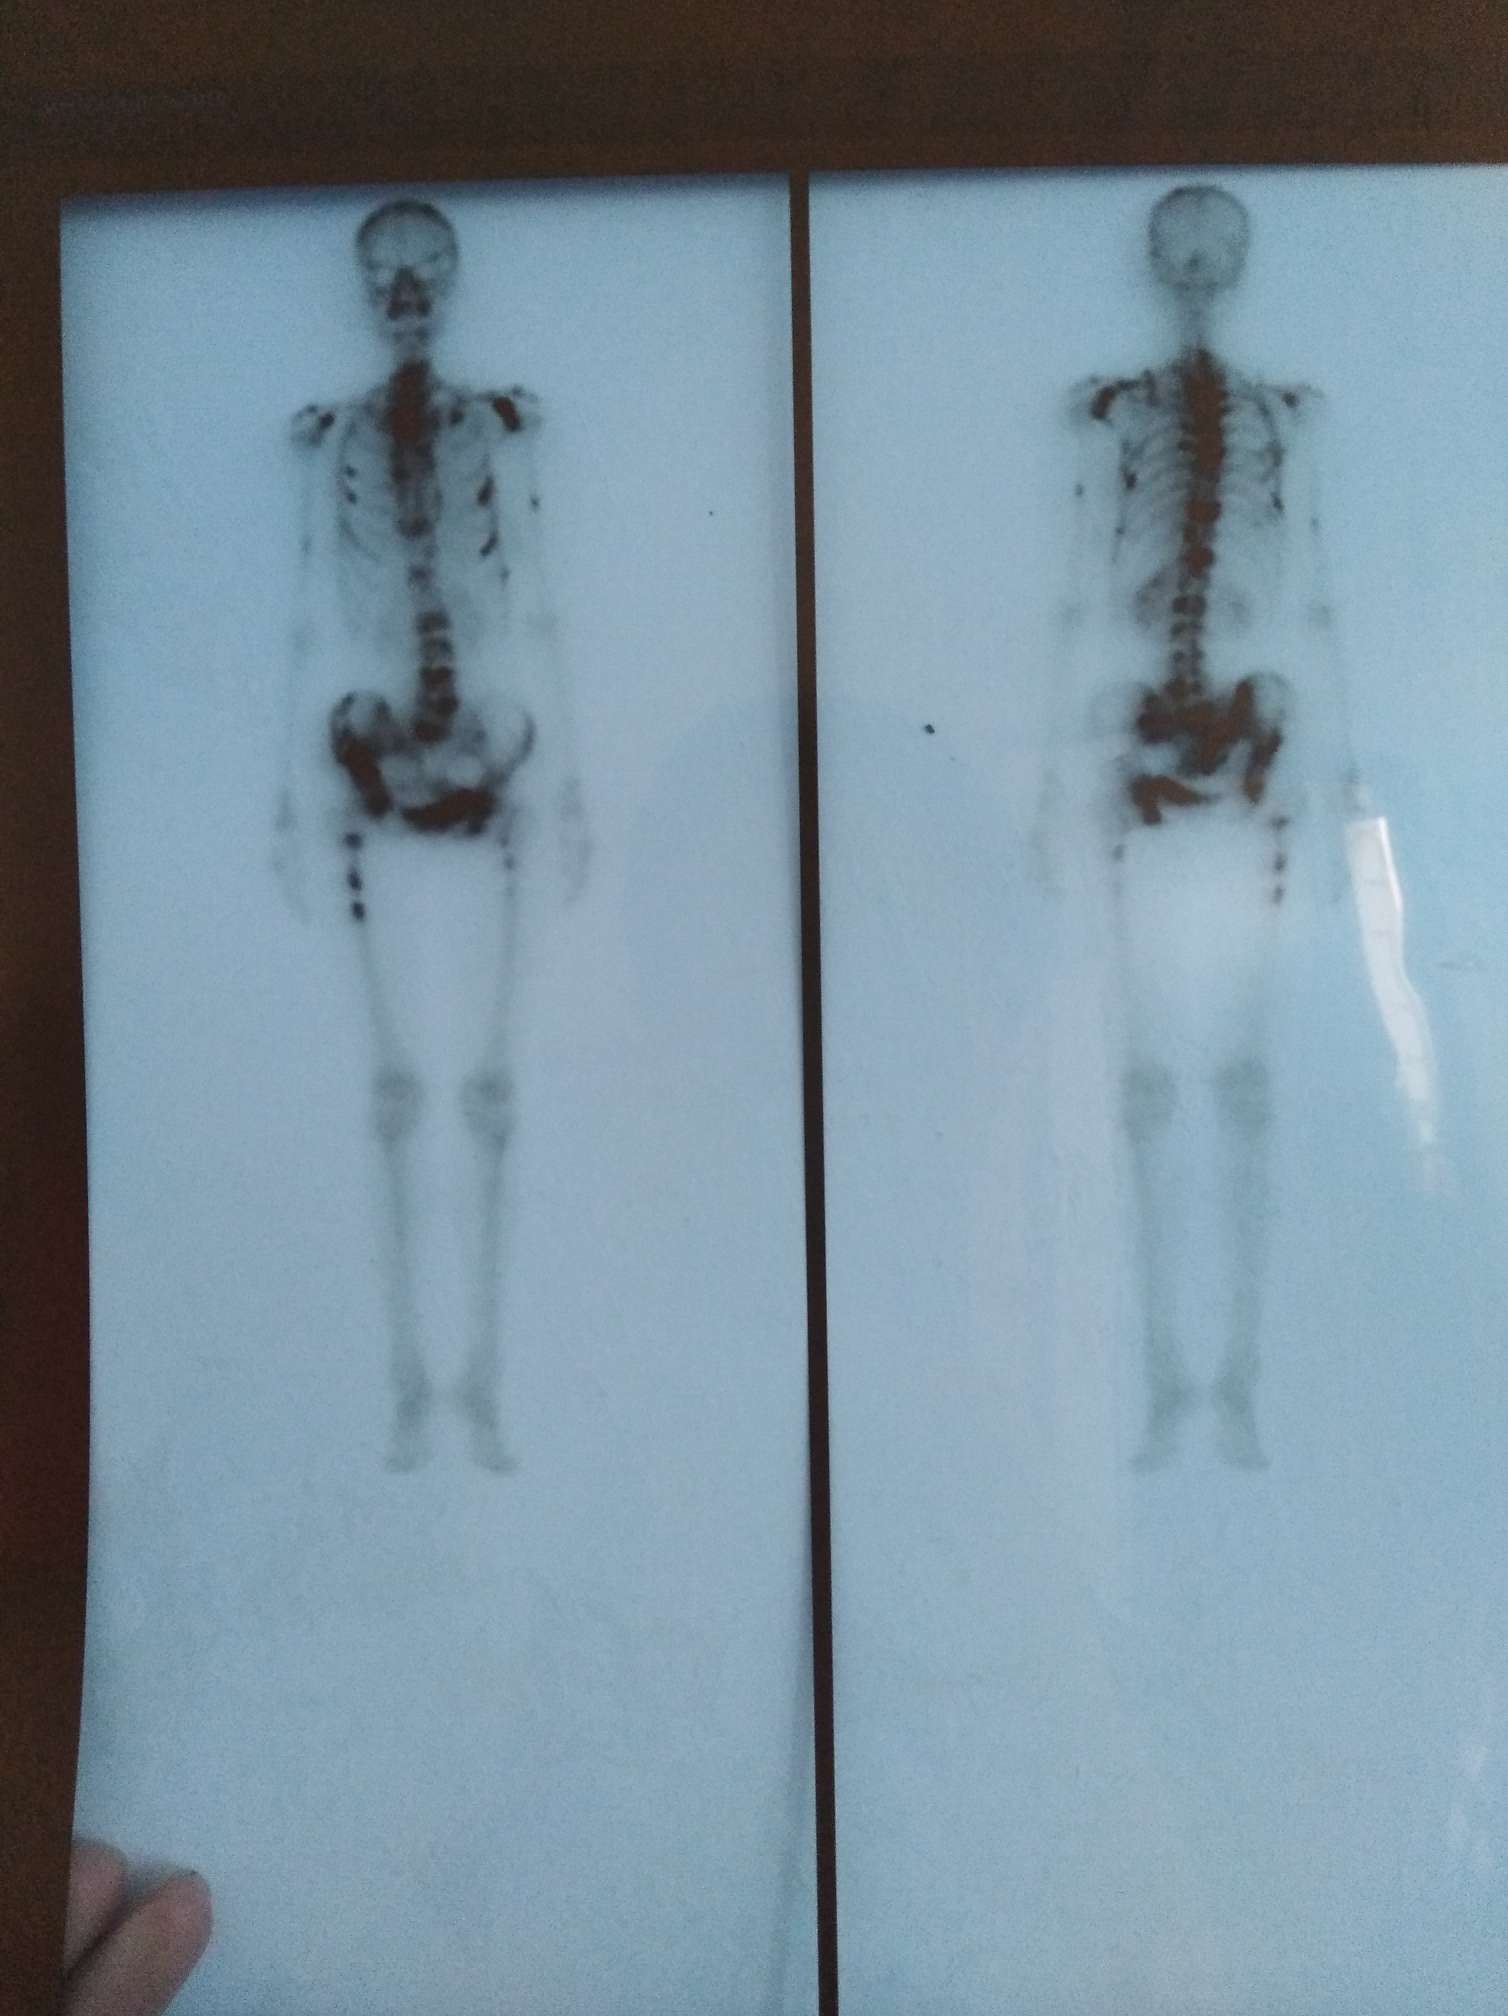

骨转加重了!

妈妈疼得厉害,我今天拿出骨扫描片子对比了下,的确这次比年前检查多了好多转移点,光平一个伊班膦酸钠还是不能拦截可恶的癌细胞,左胳膊疼痛加麻木,手已经不会动了,图一是18年11月片子,图二是19年9.26片子,骨转移的朋友们你们都在怎么治疗呢?吃药还是放疗?